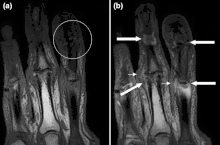

Magnetic resonance image of the index finger in psoriatic arthritis (mutilans form). Shown is a T2 weighted fat suppressed sagittal image. A focal increased signal (probable erosion) is seen at the base of the middle phalanx (long thin arrow). There is synovitis at the proximal interphalangeal joint (long thick arrow) plus increased signal in the overlying soft tissues indicating edema (short thick arrow). There is also diffuse bone edema (short thin arrows) involving the head of the proximal phalanx and extending distally down the shaft.